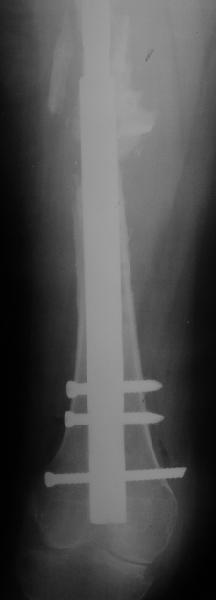

Female, rheumatoid, THA in 2003, car accident in 2006, failed plating. Nailing in Oct 2007. The nail is solid with hollow proximal part where the stem is docked. Last images are in 1 year after

nailing.

I have refreshed respect for the mighty femur and it’s incredible/remarkable ability to unite, regardless of what we do to it.

The femur responded by failure to Mennen plating (DePuy Bridge plate). So i would add that the ability to unite is realized in mechanically and biologically sound conditions.